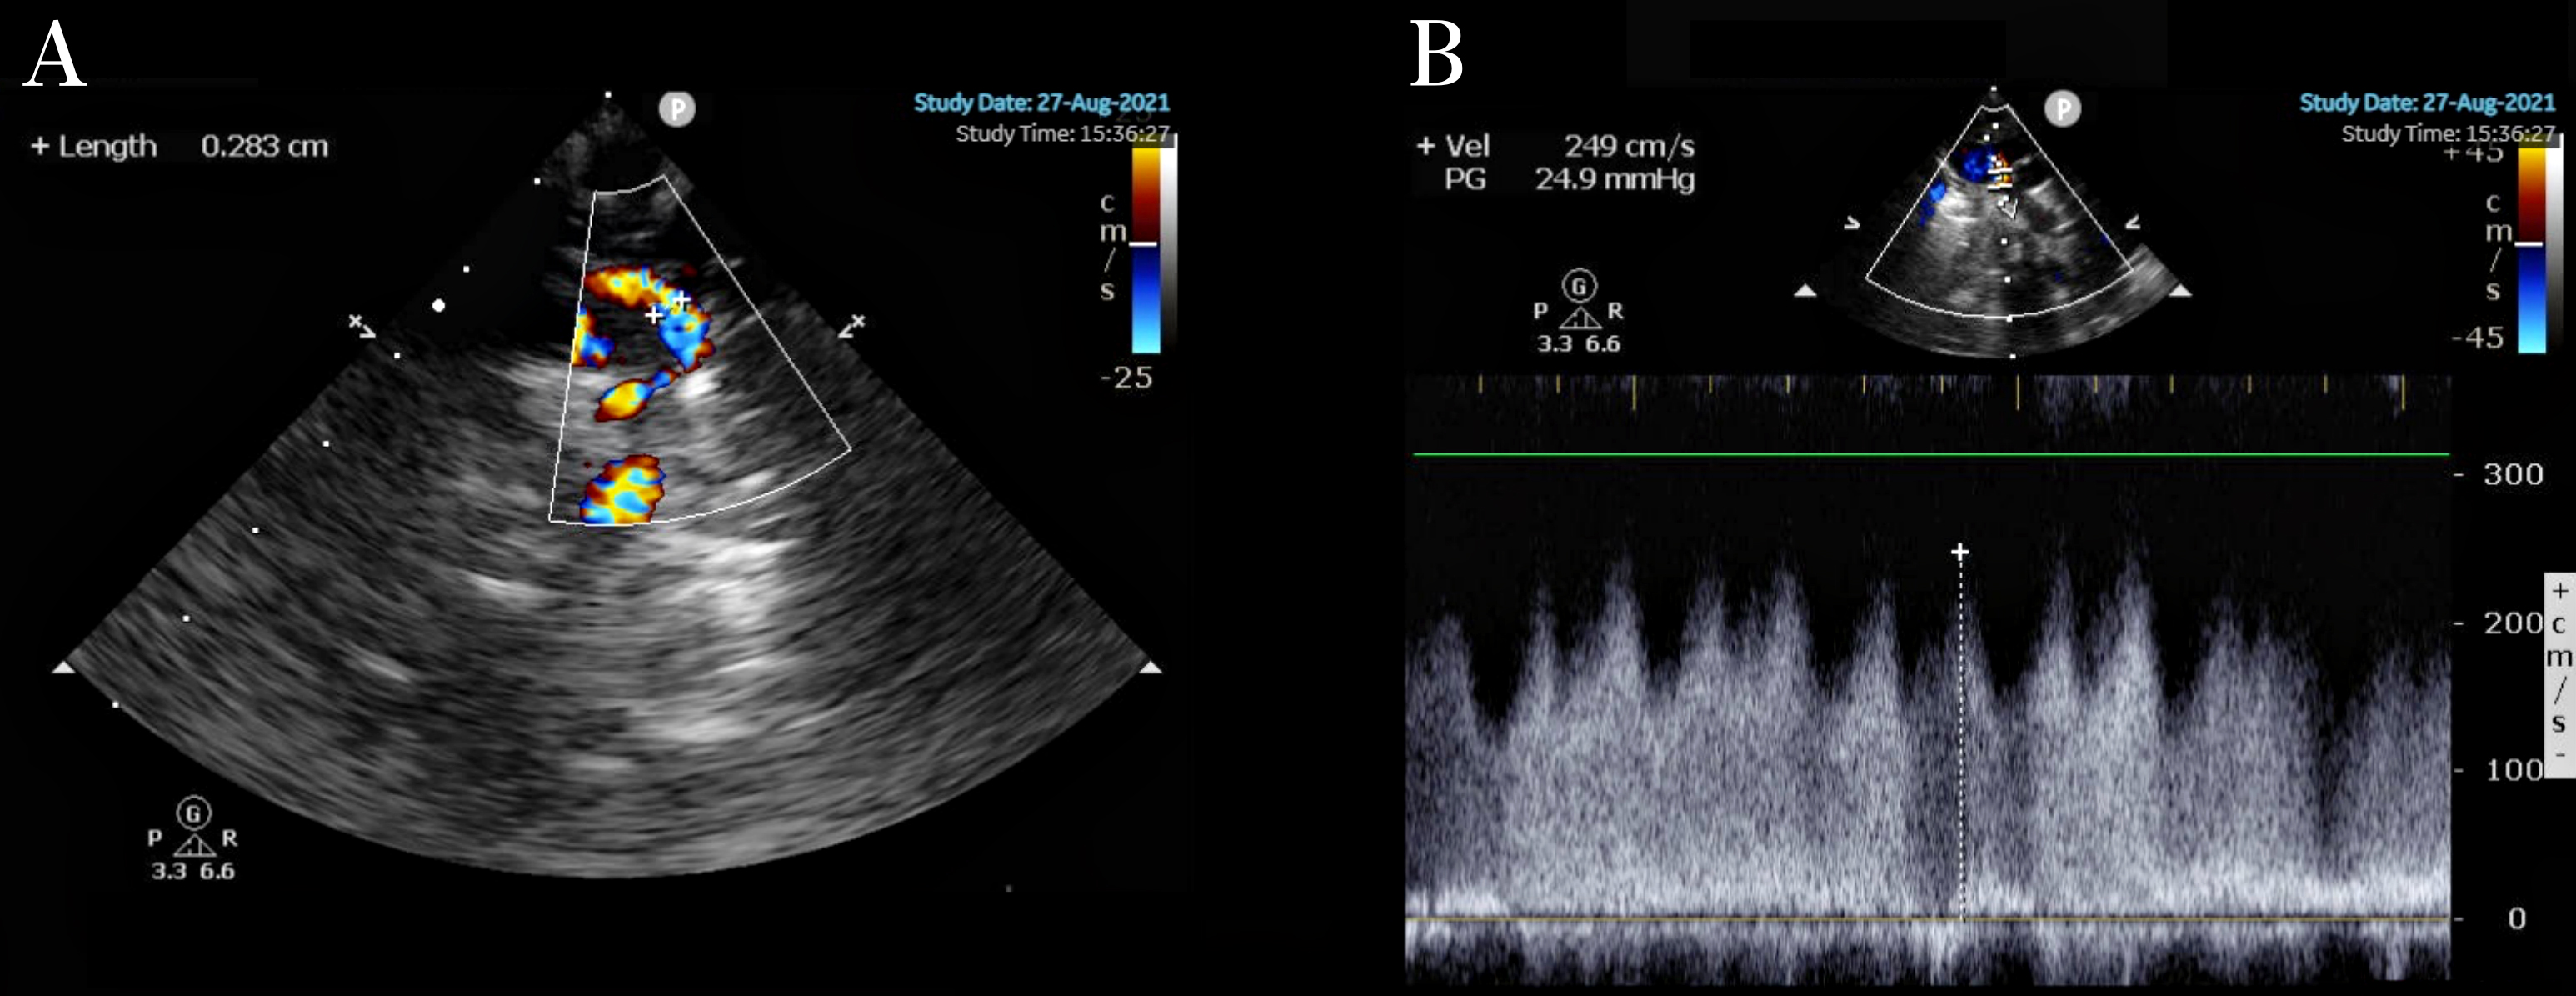

Fig. 2.

Supracardiac TAPVC. (A) Diameter of the obstructed vertical vein: 0.283 cm. (B) Vertical venous flow velocity 2.49 cm/s.